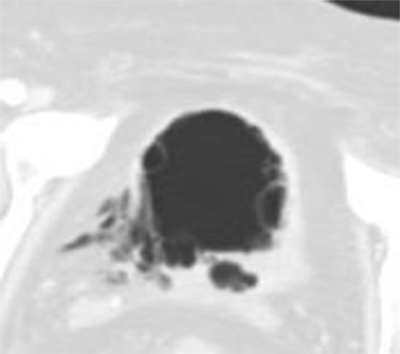

Figure 2

Same Axial unenhanced CT-scan image as above in Lung Window shows fibrotic tissue at the disrupton site. There are multiple air-filled submucosal blebs of the bladderwall suggesting an emphysematous cystitis.